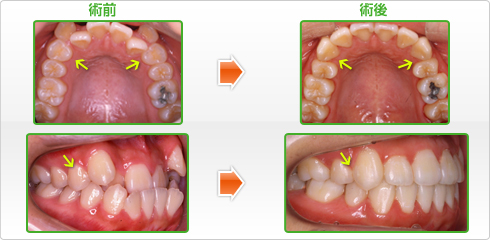

矯正治療とは、八重歯、乱杭歯(凸凹)、受け口、出っ歯、すきっ歯のような悪い歯並びや、かみ合わせ(不正咬合)をきれいに揃えて、上と下の歯の咬み合わせを良くし、 これによって口もとの形を整えると同時に、食べ物を良く咬めるようにすることを目的としている治療です。 これに加えて、発音を明瞭にさせるとともに、虫歯や歯槽膿漏になることを防ぎ、健康を一段と増進させようとするものです。きれいな歯並びに整った容姿は、明るく、積極的な性格をもたらしてくれることでしょう。

治療方法